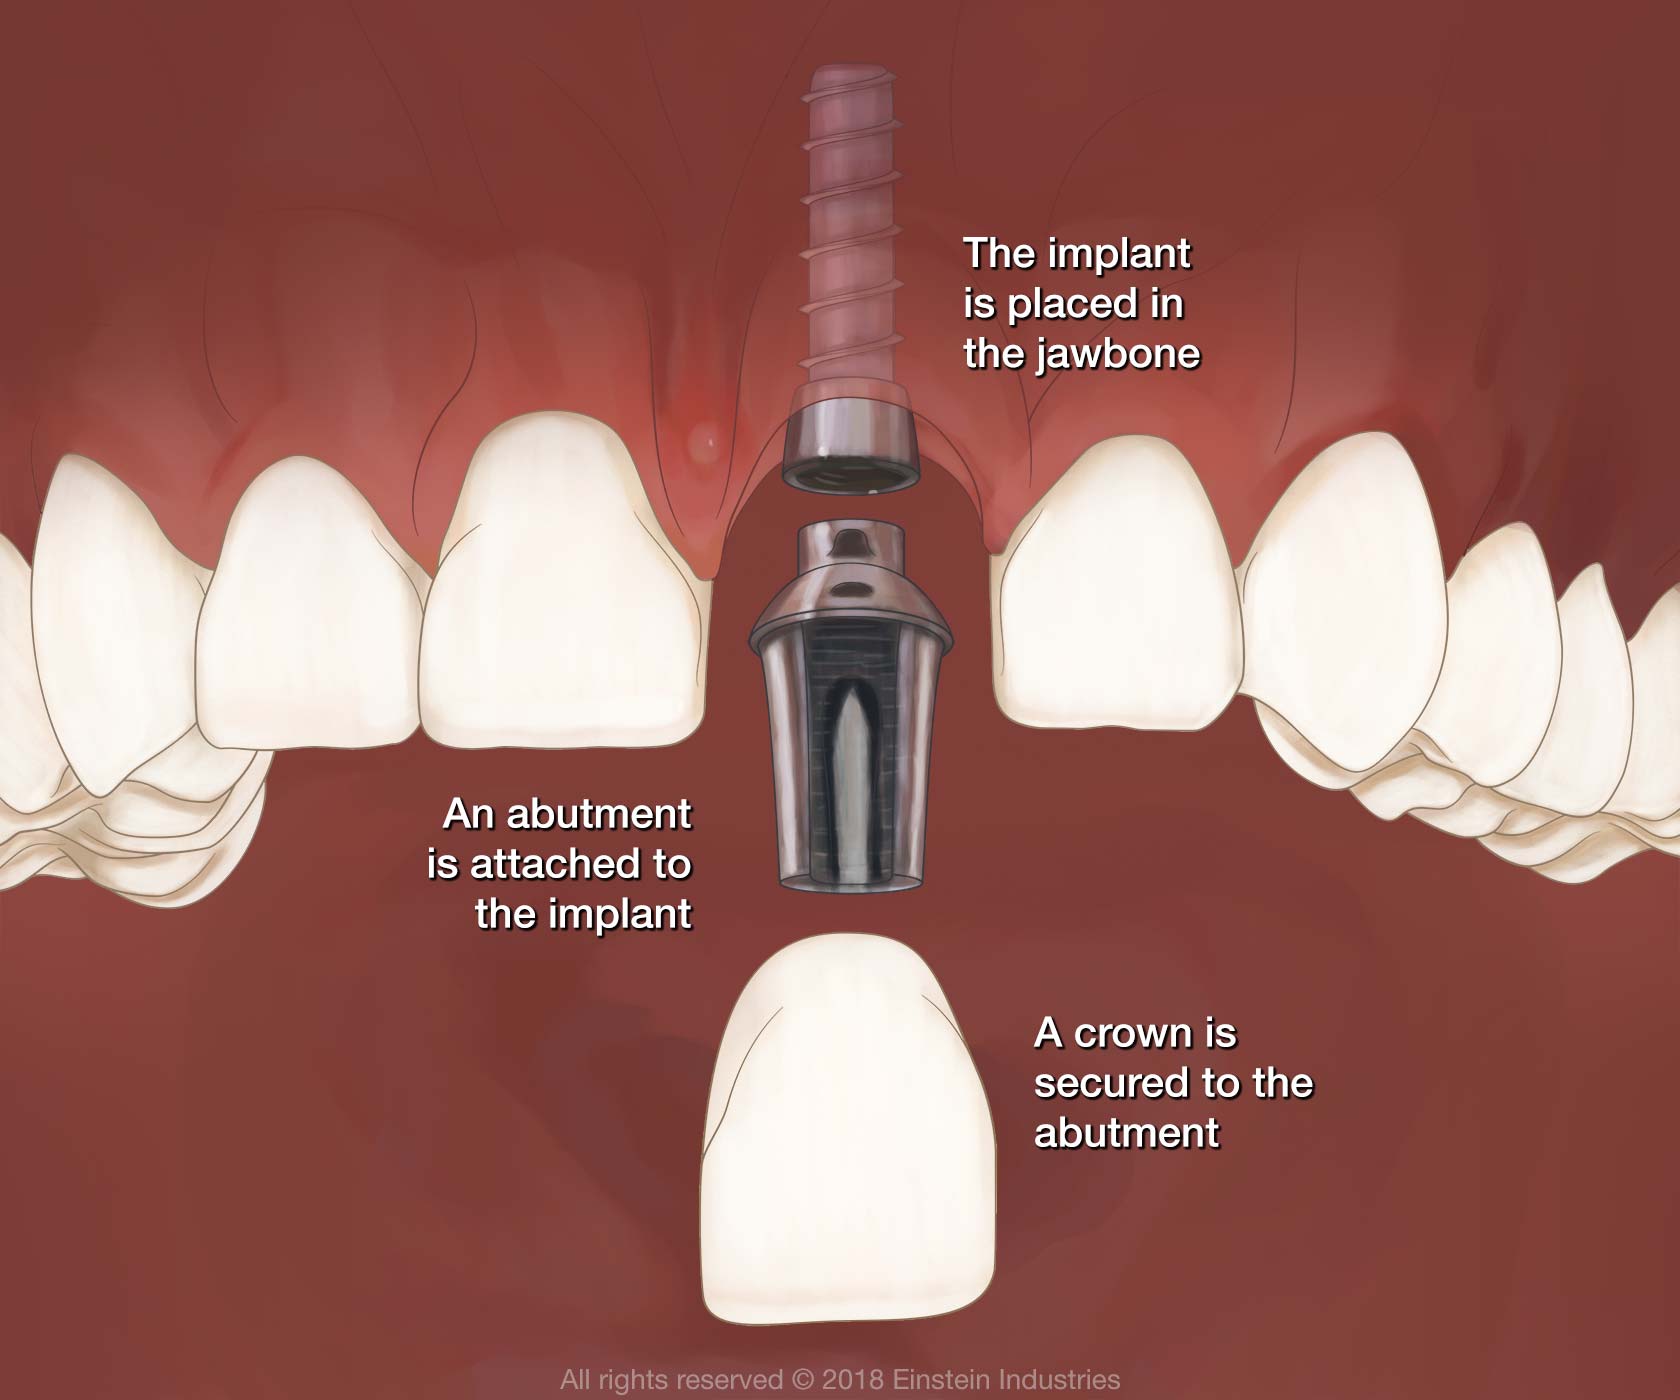

The Anatomy of The Dental Implant | Knoxville TN Dentist

What is a Dental Implant? | DDi

Dental Implant, Single Tooth

How dental implants work – Dental News Network

How do dental implants work? ⋆ Dental House

Dental Implants Portland OR | What Are Dental Implants